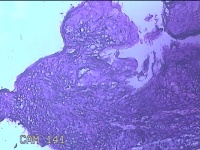

左大腿内侧包块

性别

男

年龄

21岁

临床诊断

脂肪瘤

一般病史

左大腿内侧起包块一月余。

标本名称

大体所见

灰白暗红色包块2.5x2x0.8cm一个,表面糜烂,切开包块呈实性,切面灰白暗红色,质软。

片子这个效果,没有胆量下诊断了。

脱水机的试剂多久没有更换了?